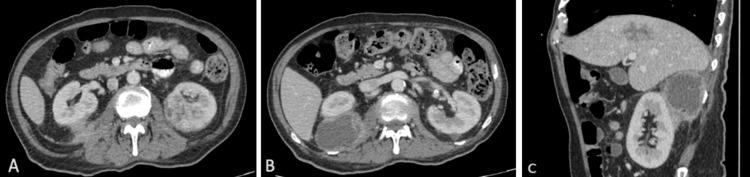

Invasive Klebsiella Syndrome With Multiple Liver and Renal Abscesses.

Invasive Klebsiella syndrome (IKS) is a significant health concern, particularly in Asia, as it results in a high mortality rate. Due to the hypervirulent strains of , it is more frequently detected among immunosuppressed individuals and will mainly metastasize to different organs, including the liver, kidneys, eyes, and brain. Here, we present the case of a 70-year-old man with underlying diabetes mellitus who developed multiple organ abscesses secondary to , requiring prolonged antibiotic treatment and abscess drainage. This case report highlights the importance of early diagnosis and appropriate antibiotic therapy to improve patient outcomes.